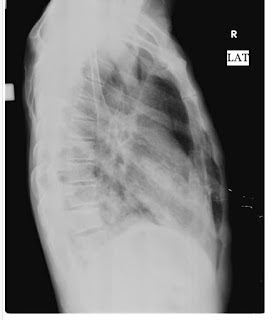

X-RayDIAGNOSIS

WITH RIGHT LOWER LOBE PNEUMONIA

RESPIRATORY EXAMINATION

INSPECTION

Shape- Flattened

Chest movements- Reduced on the right side

Vocal fremitus-reduced on the right side

Right side dull note at mammary and inframammary areas

Right side - breath sounds reduced

Findings: 1)E/O air bronchogarm in right lung

2) right lung consolidation